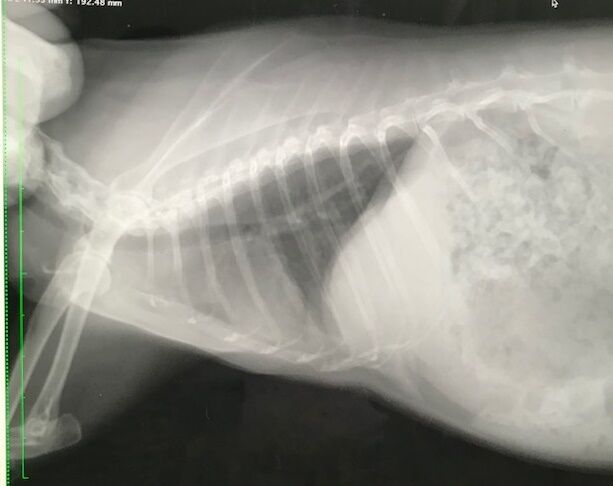

その後も糞はいくつか出てたが食べる方がまったくだったので連行

キャリーがイヤなのか、もしくは相当弱ってるのか、や、痛みに俄然弱いタイプかも?

ので、さすがに胃の張りとかはない

体重は1.96kgで甘えたさんは全開

異変から改善なく通院コースになるのも珍しく、

まあせっかく来たし?点滴もしてもらいました。

ステロイドも少しだけ。